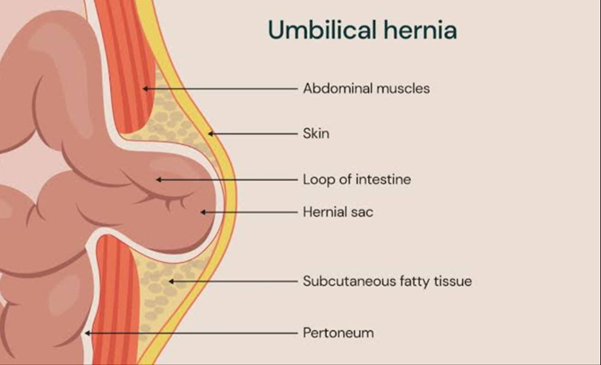

An umbilical hernia happens when a part of the intestine or abdominal tissue pushes through a weak spot in the abdominal muscles near the belly button (navel).